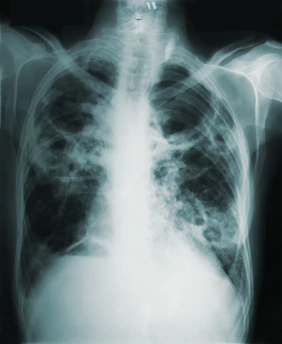

Diagnosis

Diagnosis involves integrating clinical information with imaging and functional testing.

Evaluation commonly includes:

detailed medical and exposure history

physical examination

pulmonary function tests to assess lung capacity and gas exchange

high-resolution computed tomography of the chest

blood tests to identify autoimmune or inflammatory causes

In some cases, a lung biopsy may be necessary to confirm the diagnosis and determine the specific pattern of lung injury.